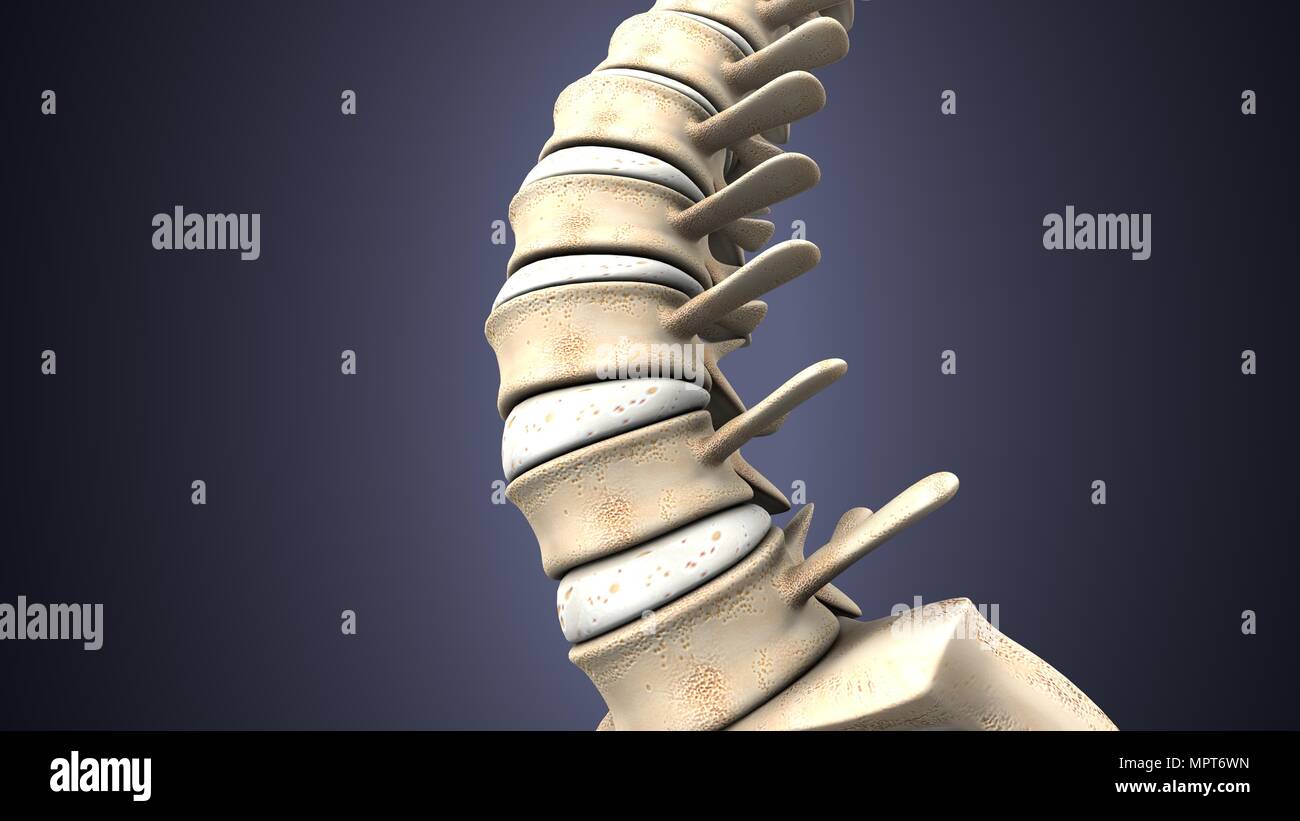

RMKRCW8B–Diagramme de l'os de la jambe droite, montrant l'articulation avec le bassin de la hanche. Date : 1908